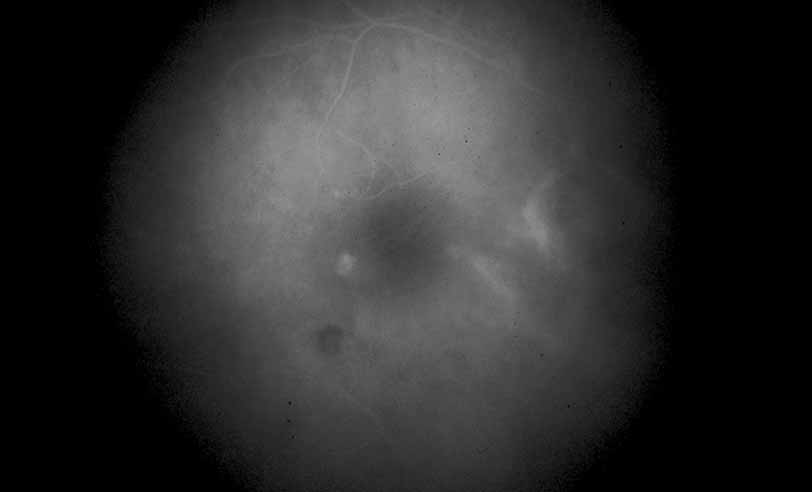

Fig. 12 Acute multifocal hemorrhagic retinal vasculitis. The patient later developed disk neovascularization with vitreous hemorrhage. Note the areas of neovascular leakage from the optic nerve.

Fig. 13 Acute multifocal hemorrhagic retinal vasculitis. The patient underwent scatter laser photocoagulation to the zones of retinal capillary nonperfusion, which resulted in regression of the neovascularization.